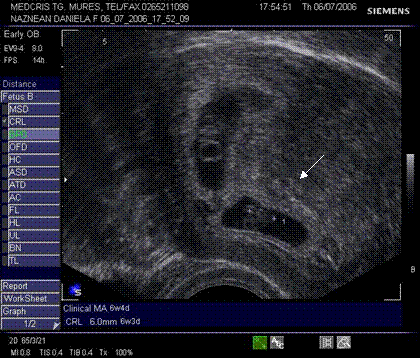

Fig nr 38. Sarcina biamniotica bichoriala 6 sapt . dupa

inseminare intrauterina cu stimulare ovariana, cele doua sageti marcheaza zona

de nidatie, respectiv placentatie, iar sacii amniotici sunt evident separati,

cu cate un embrion

Fig nr 39

Prezinta aceeasi sarcina biamniotica bichoriala,ca in figura precedenta, cu

semnul lambda marcat cu sageata